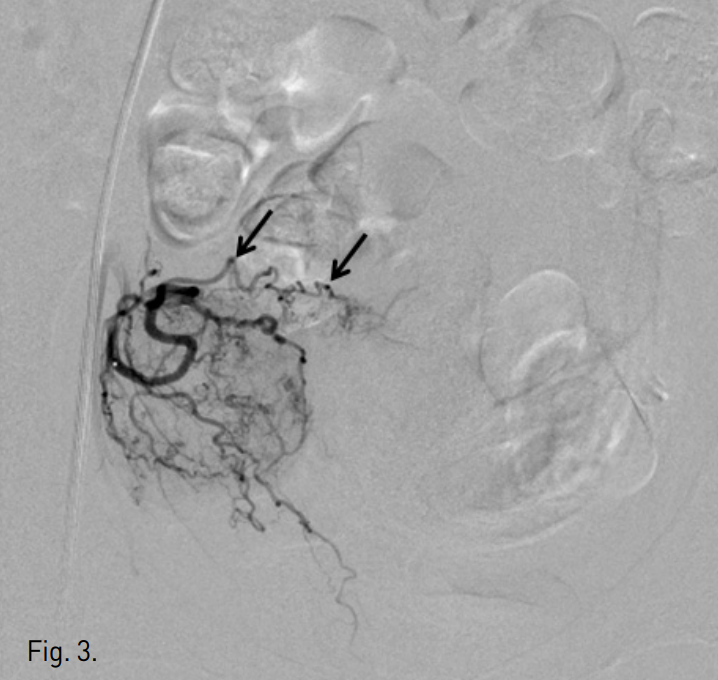

초음파 유도하에 우측 대퇴동맥을 천자하여 5F sheath(Terumo, Tokyo, Japan)를 삽입하였다. Pigtail 카테터(Cook, Bloonington, IN, USA)를 하부 대동맥에 위치시킨 후 골반조영술을 시행한 결과, 좌측 자궁동맥의 비대가 관찰되었다(Fig. 2a). 양측 자궁은 각각의 자궁 동맥으로부터 영양 공급을 받고 있었으며 두 동맥은 거의 서로 연결되어 있지 않았고 완전히 독림된 자궁이 조영되었다(Fig. 2b). 5 F Cobra 카테터(Cook, Bloonington, IN, USA)로 좌측 내장골동맥에 진입시키고 Microferret 카테터(Cook, Bloonington, IN, USA)로 좌측 자궁동맥을 선택하였다. 자궁동맥의 상행분절에 Microferret 카테터를 위치시키고 polyvinyl alcohol(PVA)(Contour, Bostonscientific, Fremint. Calif)을 이용하여 자궁동맥 색전술을 시행하였다. 150-250 micrometer, 250-355 micrometer, 355-500 micrometer의 PVA를 순서대로 사용하는 1-2-3 프로토콜로 색전술을 시행하였다. 이때 조영제와 식염수가 1:1로 섞인 용액에 PVA입자를 넣어서 총 60ml를 만들었는데, 각각의 사용한 양은 20cc( 1/3 vial), 40cc(2/3 vial), 20cc(1/3 vial) 이었다. 10 번의 심장박동 동안 자궁 동맥내에 조영제의 정체가 보일 때까지 색전술을 시행하였다. 우측 자궁동맥 조영술에서 좌측 자궁과 연결 되는 작은혈관이 관찰 되었으나 향후 체외수정을 고려하여 색전술을 시행하지 않았다(Fig. 3). 색전술 후 3개월째 시행한 MR에서 선근증 완전괴사를 관찰할 수 있었으며 좌측 자궁은 44.3%의 볼륨감소를 보였다(Fig. 4a-b). 시

술 전 증상을 10점으로 가정했을 때 생리양의 경우 10점에서 5점, 생리통은 10점에서 0점으로 감소하였다.

Fig. 4

A, B. T2 weighted (A) and contrast enhanced (B) MR images taken three months after embolization show 44% volume reduction of the left-sided uterus and non-perfusion area in adenomyosis (arrows in A and B).